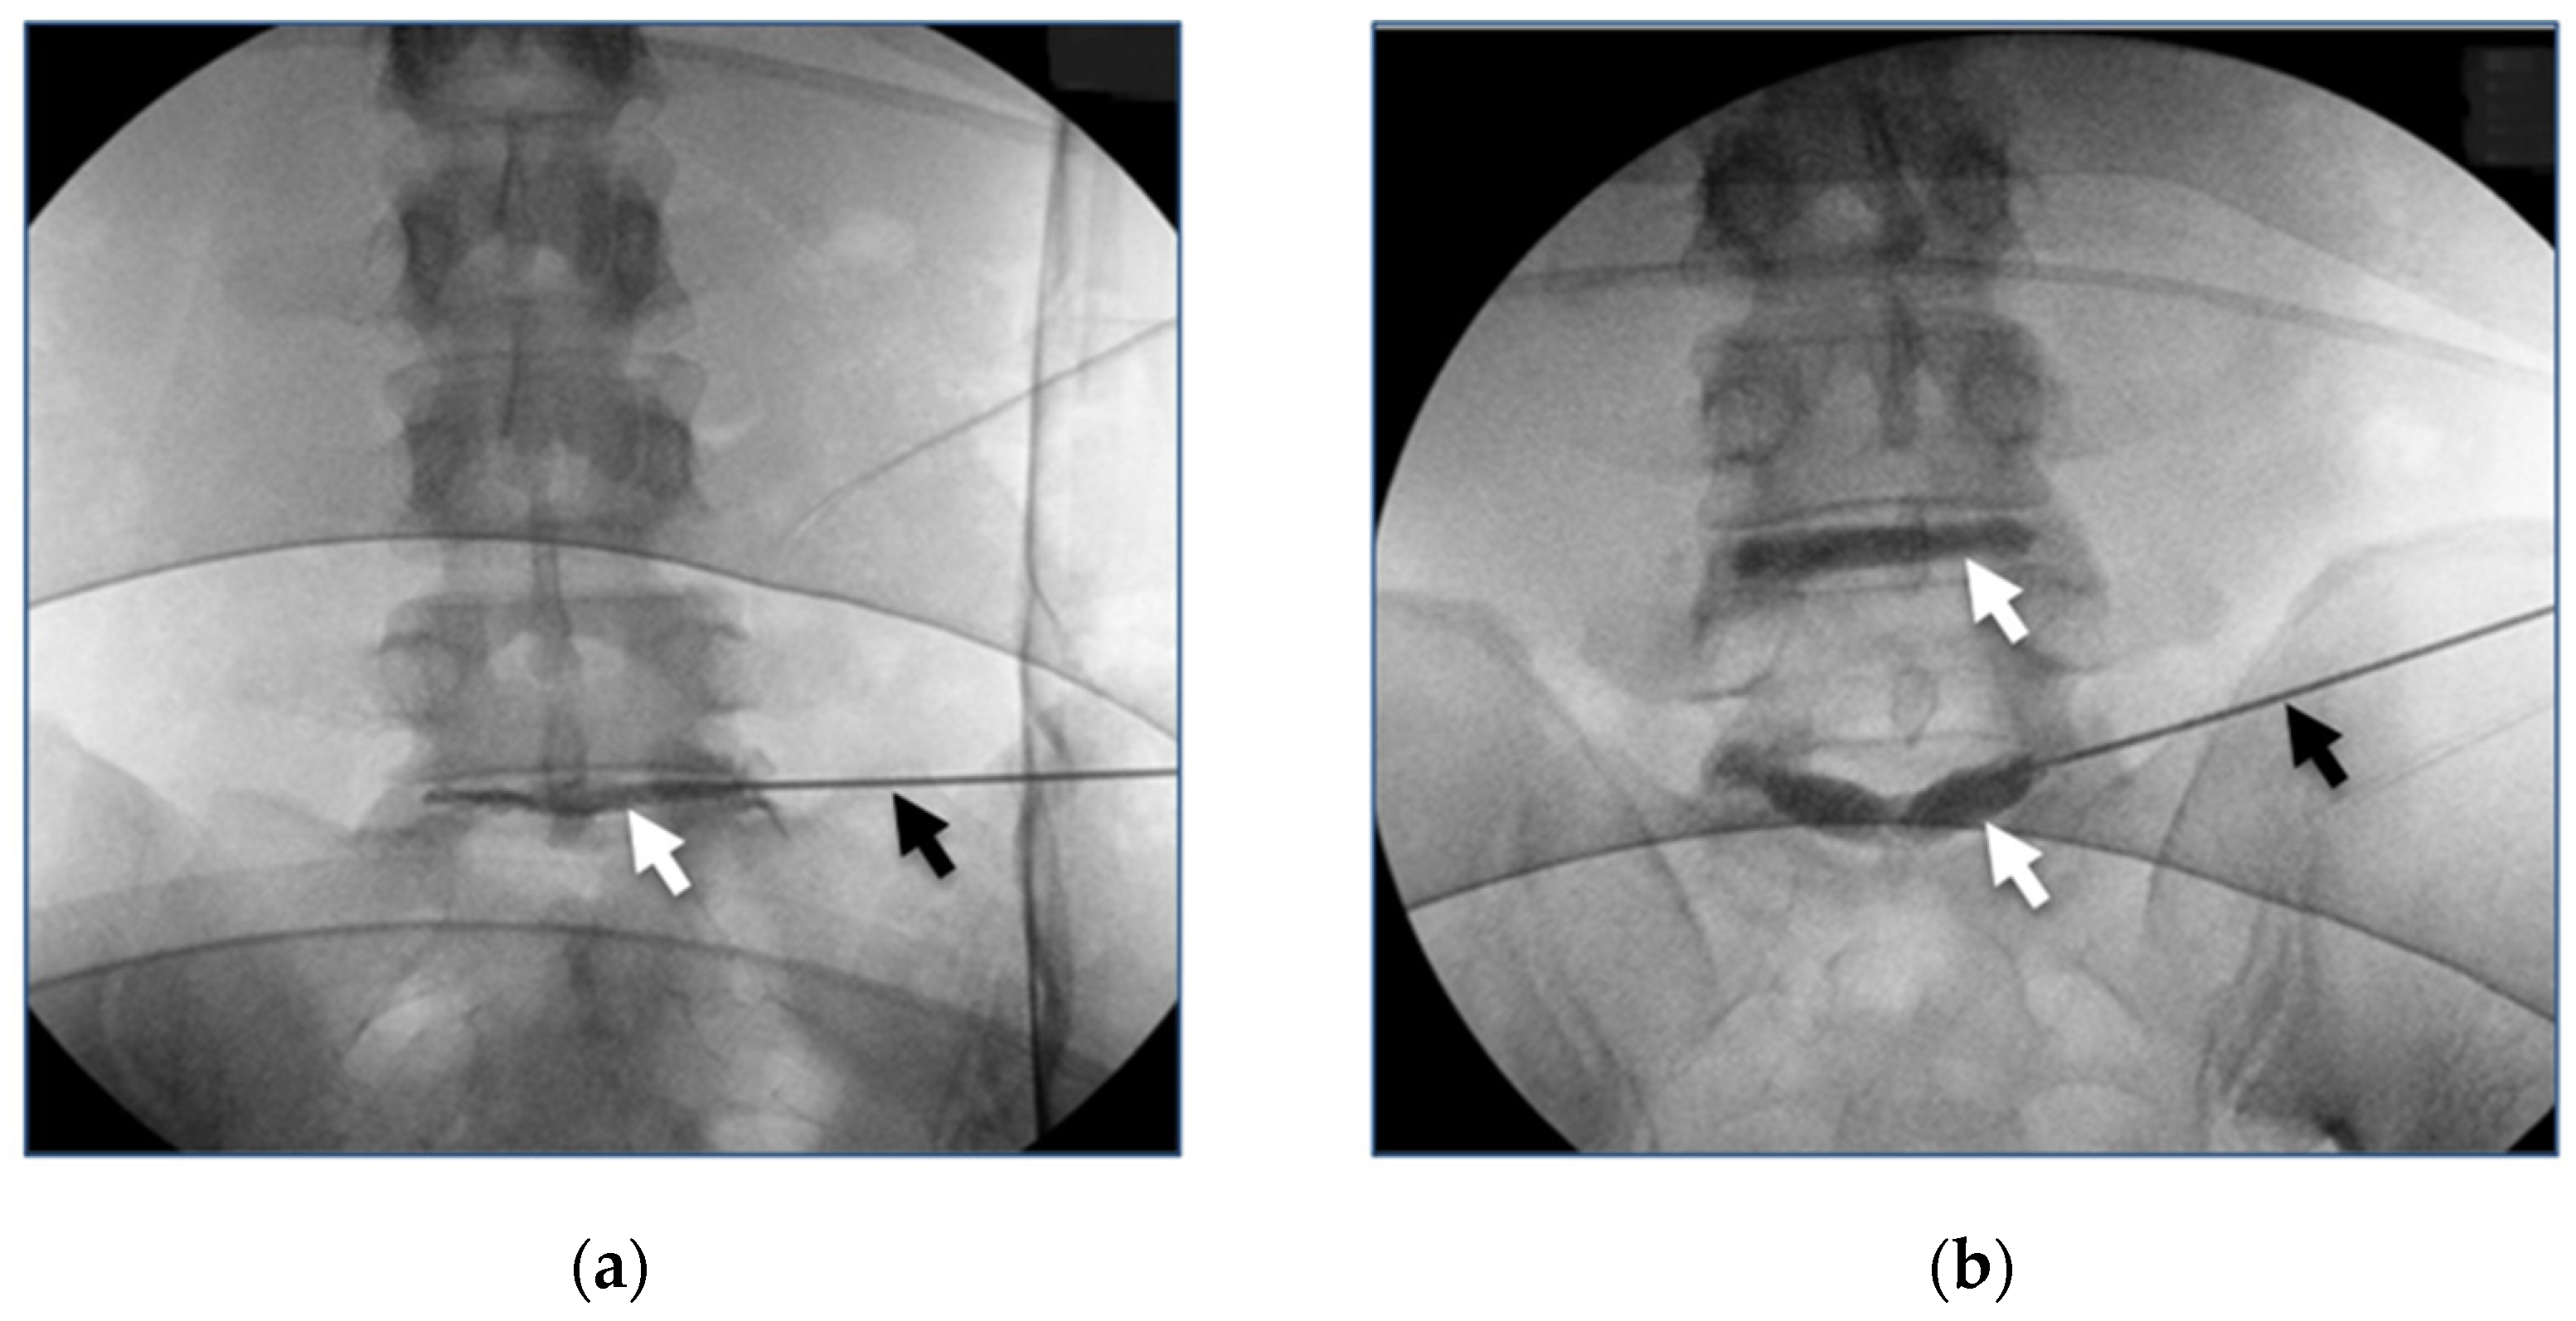

- Hedman, T.; Yu, J.; Singh, H.; Deer, T. Early clinical results of intervertebral joint stabilization by injectable load-sharing polymers. J. Pain Res. 2023, 16, 2777–2789. [Google Scholar] [CrossRef] [PubMed]

- Lin, H.J.; Lin, L.C.; Hedman, T.P.; Chen, W.P.; Chuang, S.Y. Exogenous Crosslinking Restores Intradiscal Pressure of Injured Porcine Intervertebral Discs: An In Vivo Examination Using Quantitative Discomanometry. Spine 2015, 40, 1572–1577. [Google Scholar] [CrossRef] [PubMed]